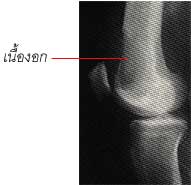

ภาพแสดงมะเร็งที่กระดูก